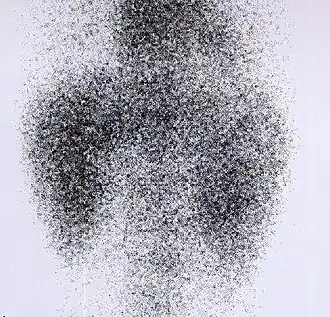

DMSA scan

![]() Decreased Tc99m-DMSA uptake in both kidneys, suggestive of renal failure. | |